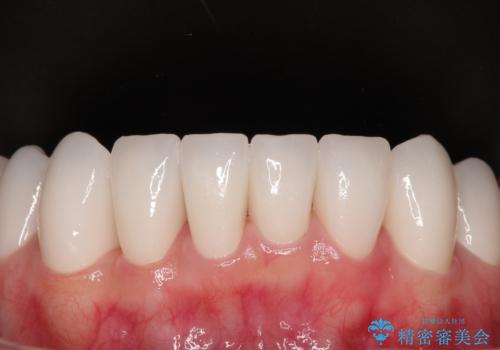

自他共に認める、非常に色白の患者様であったため、黄ばんだ歯の色を白くすることを希望されており、歯周病治療の該当部位に限らず、全顎的にオールセラミッククラウンにて補綴治療を行うこととしました。

多くの外科処置を行ったため、治療期間も長くなり、患者様の負担は非常に大きなものとなりましたが、明るく健康的な口元となり、患者様には大変満足していただけました。